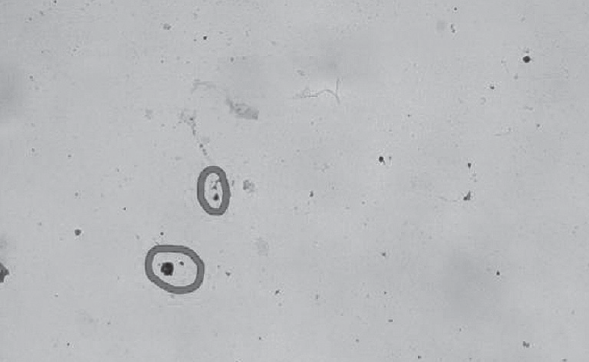

Materials and methods. Under the supervision of pediatricians of the Department of motherhood and childhood of the St. Petersburg AIDS Center, there were 388 HIV-infected children aged from one month to 17 years inclusive. Due to the reasons of late detection and HIV dissidence of parents, 18 children (4%) died cumulatively among the children observed in St. Petersburg center for AIDS. The object of the immunohistochemical study was randomly selected HIV-infected children who applied to the center for prevention and control of AIDS for return visits. Material for testing for the presence of HIV-1 P24 antigen was taken from the back wall of the nasopharynx.

Results. When analyzing the ways of HIV infection in children registered at the maternity and childhood Department of the Saint Petersburg AIDS Center, it turned out that 363 children were infected perinatally (93,6%), 23 (5,9%) sexually infected and 2 children through injecting drugs (0.5%). The proposed method of immunocytochemistry for the diagnosis of HIV infection in children can find its application, especially for primary diagnostics, which may simplify and reduce the cost of laboratory diagnostics.